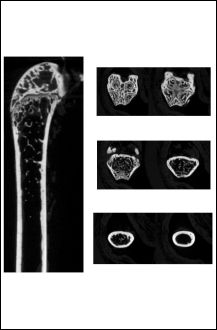

大鼠膝关节CT展示